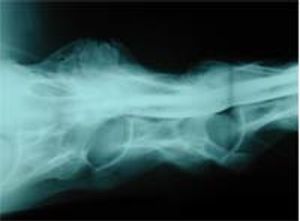

Osteoarthritis and cervical pain can present with clinical. Almost all skeletal preparations of horses over 18 years old have evidence of arthritic changes.

Physical examination of the horses with cervical neck pain indicates reduced to poor cervical flexibility.